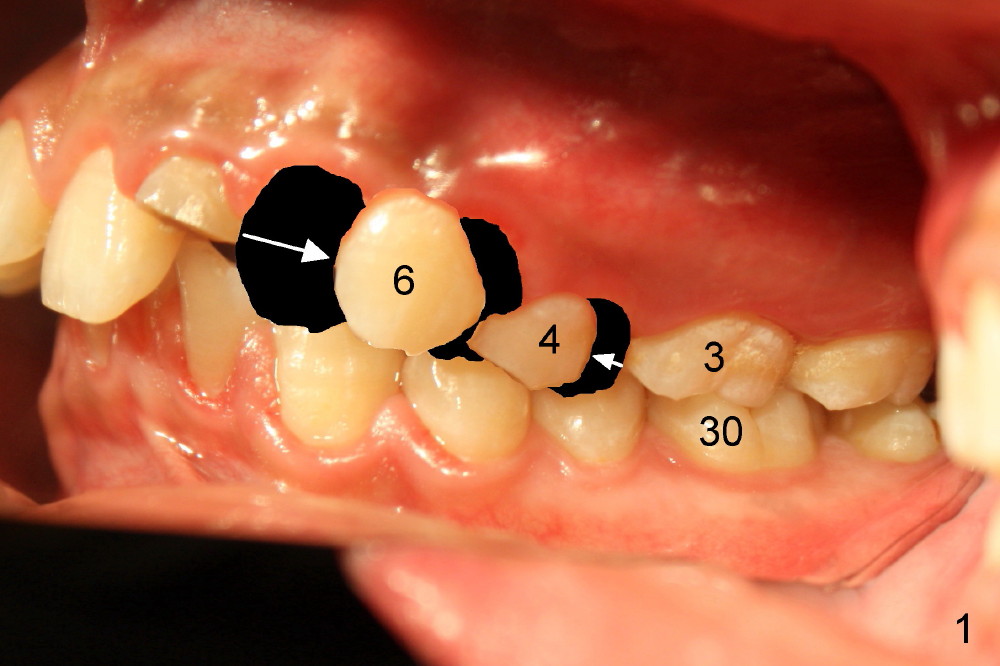

A 21-year-old man has severe maxillary protrusion (Class II malocclusion) with crown fracture of #7 (Fig.1,2,3 (latter two mirror images). Treatment plan is to place pre-fabricated post and provisional for #7 (Fig.4,5 C) and start ortho treatment with extraction of upper 1st bicuspids (Fig.5 *, <). When ortho finishes, fabricate full-coverage porcelain crown for #7.

The 1st step of ortho is arch wire sequence to align the arches (from thin round wires to thick rectangular ones). The 2nd is to retract the canines distal (Fig.1 (planning), Fig.7 (6 months post bracketing), Fig.8 (7 months), using closed coil springs (*). The 3rd step is to move the remaining anteriors together distal using posted wire (^) and again closed coil springs (Fig.9; 8 month into treatment). Note the overjet between upper and lower anteriors (Fig.9: *). This space allows the upper incisors to move backward.